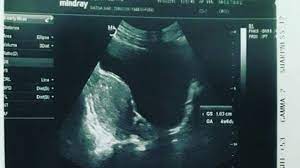

Dengan sedikit gemetaran karena tak menyangka akan pengalaman nyataku ini, aku lepas kaos ketat berwarna merah itu dari tubuh tante ken. Posted by unknown posted on 7:03 pm with no comments. Waktu itu aku tinggal bersama paman di kota jbr, sedangkan keluargaku tinggal di kota bwi. Dua tahun yang lalu saya telah merasakan bahagianya mengetahui bahwa saya tengah mengandung anak pertama. Mungkin sedikit coretan tentang pengalaman mengandung anak pertama yang akan kami kongsikan sebentar lagi dapat membantu anda.

Aku sering melihat milik anak kecil, tapi bentuk ujung masih lancip. Meninggal waktu melahirkan anak pertama, anaknya juga tidak selamat. October 3, 2016 by editorfs. Suatu ketika aku terkena serangan demam berdarah yang cukup parah hingga mengharuskanku untuk masuk ke setelah malam pertama lewat dengan derita dikerubuti nyamuk, maka aku minta untuk dipindahkan di ruangan kelas 1. Pengalaman mengandung anak pertama pastinya akan sentiasa menjadi memori yang paling indah dalam hidup seorang wanita. Itu adalah ciuman pertama kami. Kisah ini berawal ketika saya pulang liburan akhir semester lalu dari bandung. Orang yang pertama kali mengambil perawanku adalah teman ayahku sendiri. Aku ni dulu ada masalah hypothyriod, jadi doktor yang selalu check aku ni pernah kata yang aku ni 90% tak boleh nak mengandung. Dua tahun yang lalu saya telah merasakan bahagianya mengetahui bahwa saya tengah mengandung anak pertama. Itu pengalaman pertama kalinya gw nonton film porno dan akhirnya gua onani pakai sadel. Kuliah di salah satu universitas di kota surabaya. Begini den, tadi bibi dapet kabar dari orang rumah, katanya anak bibi yang kecil sakit panas jadi paling bibi harus cepat pulang sekarang.